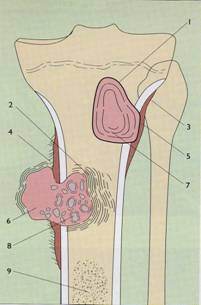

Proceduri diagnostice:

- radiografii osoase: osteoliza,

osteoscleroza sau lez mixte, reactie periostala, distructie corticala

- CT & RMN apreciaza extinderea os si

extracompartimentala a tu

TO: Benign vs Malign

TO: Clasificarea TO